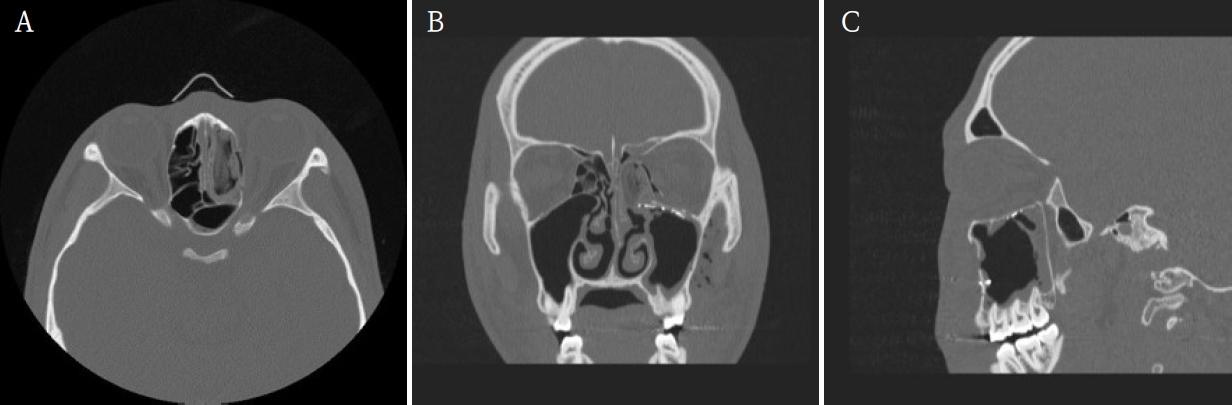

A maxillofacial CT scan was performed for further evaluation. CT imaging demonstrated fractures of the left medial orbital wall, inferior orbital wall, and nasal bone (Fig. 1). The medial wall defect was located adjacent to the ethmoid sinus with partial herniation of orbital soft tissue. The inferior orbital wall fracture extended posteriorly with minimal displacement of the bony fragments, and a depressed nasal bone fracture was also confirmed.

Preoperative maxillofacial computed tomographic images demonstrate the fractures of the left medial orbital wall, inferior orbital wall, and nasal bone. A. Axial view. B. Coronal view. C. Sagittal view.